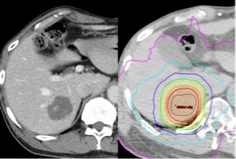

2018年以降、III期肺がんに対する化学放射線療法後に維持療法として免疫チェックポイント阻害薬が導入され、治療成績が大きく向上しました。しかし、いまだに18-30%の方が放射線照射範囲内からの再発を来すと報告されています。また、局所制御向上目的に米国にて線量増加試験(第3相試験:RTOG0617)が行われましたが、線量増加群(74Gy)でむしろ全生存率、無再発生存率が低下するという結果となりました。そこで当院および関連施設では定位照射の技術を応用し、病巣の中心部は線量を増加し辺縁は急峻に線量を下げる照射法を始めています(下図のSIB-IMRT)。すなわち、腫瘍に対しては高線量を投与すると同時に周辺組織の線量は低減することが可能となりました。この方法の治療成績や有害事象について現在解析しています。